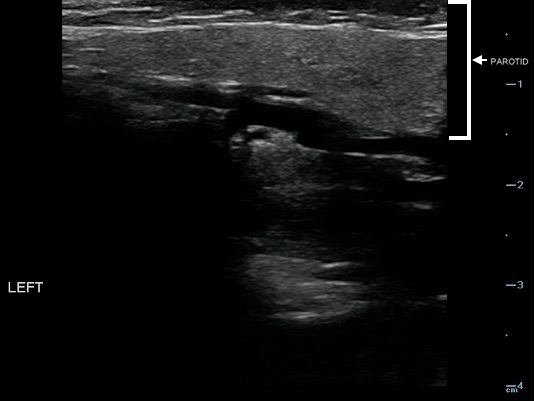

- Figure 18. Normal parotid gland (marked with arrow)

- Sonographically, the normal parotid and submandibular glands appear homogeneous; the fatty glandular tissue composition causes an increased echogenicity relative to adjacent muscle.

- Parotid Gland:

- The homogeneity and echogenicity of the parotid gland is comparable to that of the thyroid gland.

- Normal intraglandular salivary ducts and the Stensen’s duct are generally not visualized with ultrasound.